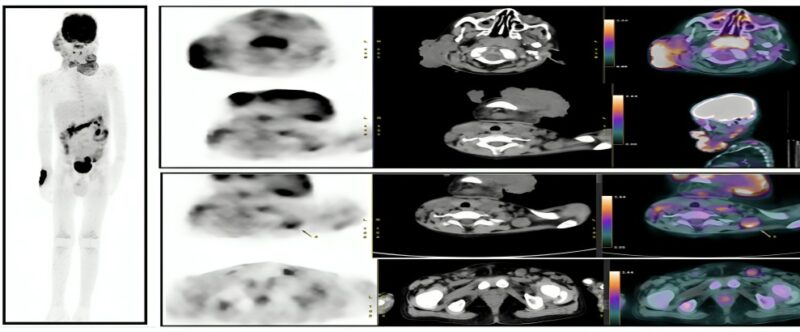

A comprehensive diagnostic workup was requested, including complete blood count, liver and renal function tests, blood cultures with sensitivity, inflammatory markers, viral serology, PET/CT (Figure 2), excisional biopsy of the facial lesion, fundus examination, orbital ultrasound, corneal scraping, as well as immunological and genetic testing.

Figure 2: Multiple metabolically active facial soft tissue lesions with metabolically active lymph nodes

Diagnostic imaging plays a key role in invasive fungal disease (IFD), including early detection, assessment of dissemination, monitoring treatment response, and identifying relapse. CT and MRI are essential for evaluating disease extent and guiding surgical decisions. FDG PET/CT is emerging as a useful tool for detecting infection and monitoring therapeutic response. Although its cost may limit routine use, it can help localize clinically occult infections and evaluate treatment efficacy—particularly when patients show clinical improvement despite persistent lesions on conventional imaging. Thus, FDG PET/CT may serve as a valuable adjunct in managing invasive fungal infections5,6,7.